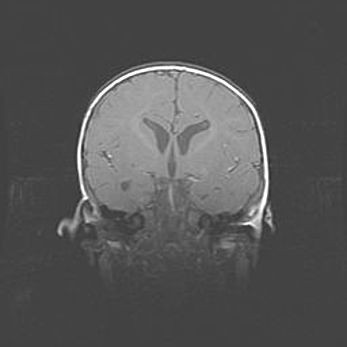

Открытая гидроцефалия.

Возраст: 6 месяцев 15 дней

Вес: 6200 г

Пол: женский

Окружность головы: 41 см

Срок гестации: 38 недель

Гидроцефалия головного мозга у новорожденных – это скопление избыточного количества цереброспинальной жидкости в головном мозге. Ее избыточное скопление в мозге приводит к патологическому расширению желудочков мозга (четырех полостей, расположенных в глубине белого вещества мозга, заполненных цереброспинальной жидкостью и связанных узкими проходами).

Открытый тип гидроцефалии (сообщающаяся) наблюдается тогда, когда нарушен механизм всасывания ликвора в системный кровоток. При этом типе причиной заболевания чаще всего является перенесенные ранее инфекции (например: менингит),  либо же наличие крови в субарахноидальном пространстве.